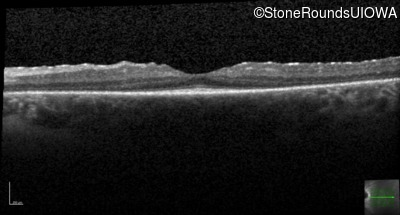

Optical Coherence Tomography - Left -

20/20 -2

Exemplar / OCT Stack